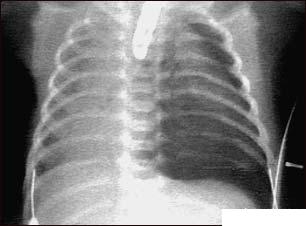

Pneumotoraxul (plamanii colabati)